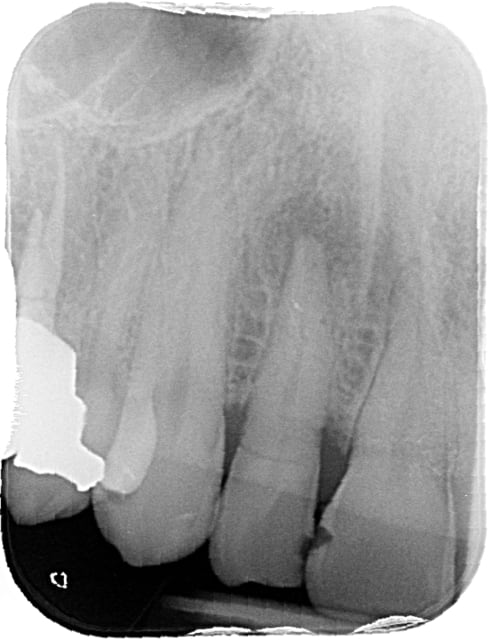

Fracture coronaire il me semble qui doit empêcher une restauration .

merci pour vos réponses, la fracture était nettement sous gingivale et je ne pensais pas pouvoir la conserver, mais c'est vrai qu'en regardant la radio ça semblait possible mais chaud quand même.